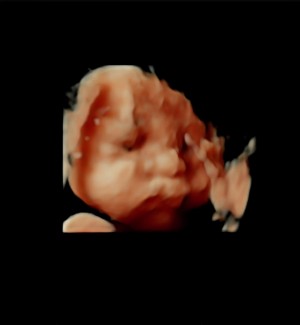

입초 두번째 만에 얼굴보여준 너!

닉네임_윤*영_5

2025-08-22

30주 입체초음파입니다 :)

이레IYRAE

2025-08-21